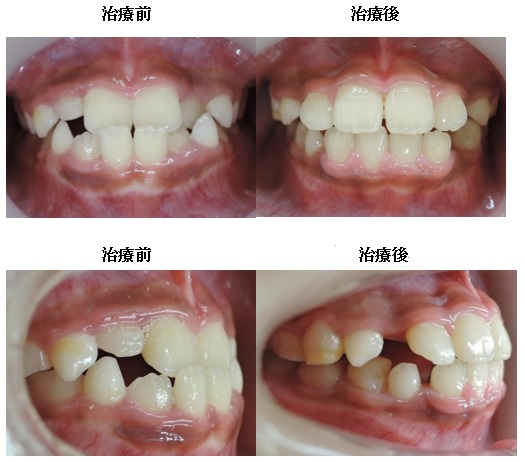

初診時12歳7か月 男子 開咬症例の治療法

矯正治療終了15歳3ヶ月

歯並びを改善すると本来の開咬状態になります。

MEAW(マルチループ)を利用して、歯を挺出させて咬合平面を変える事で下顎骨を回転させて開咬を改善していきます。

矯正治療終了15歳3ヶ月

通常の治療法としては臼歯部を圧下して治療することが多いのですがMEAW(マルチループ)の優れた点は咬合平面を変えて下顎骨を移動する事にあります。そのことにより外科矯正(骨切り)が必要か?という難症例の開咬

(オープンバイト)であっても歯を抜かないで外科矯正をしないで治療する事が可能です。